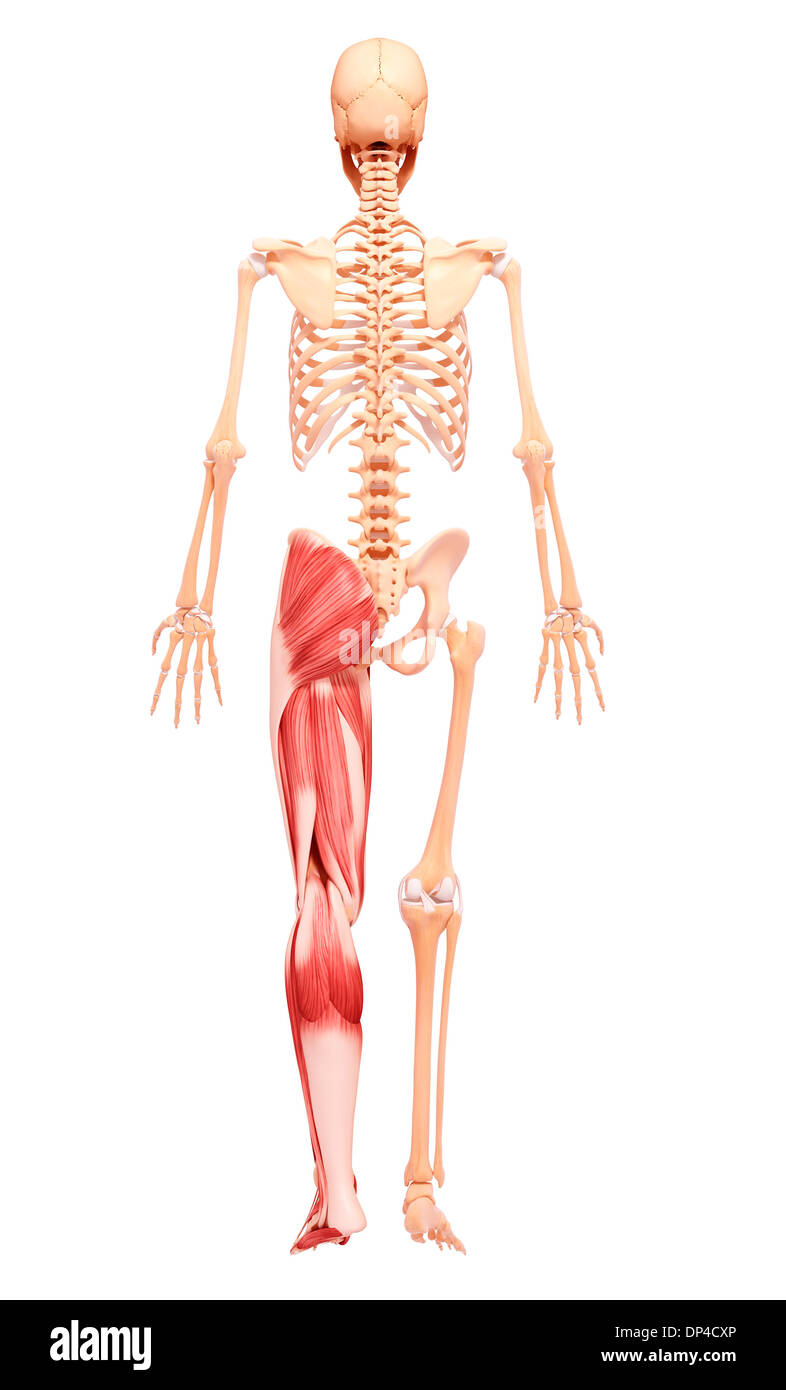

Human Skeleton, artwork Banque D'Imageshttps://www.alamyimages.fr/image-license-details/?v=1https://www.alamyimages.fr/human-skeleton-artwork-image65251506.html

Human Skeleton, artwork Banque D'Imageshttps://www.alamyimages.fr/image-license-details/?v=1https://www.alamyimages.fr/human-skeleton-artwork-image65251506.htmlRFDP4CXX–Human Skeleton, artwork